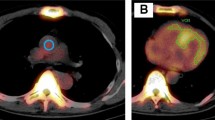

Figure 1 shows an example of SPECT/CT volumetric evaluation. We used xSPECT Quant (Siemens) to calculate SUVmax, SUVmean, and volumetric parameters. We measured 99mTc-PYP activity in an aortic blood pool using SUVmax. A spherical volume of interest (VOI; diameter equivalent to half that of the aorta) was positioned in the center of the ascending aorta at the level of the pulmonary artery bifurcation on fused SPECT/CT images.10,21 A polygonal VOI was manually placed to include uptake by the left and right ventricles, but not adjacent ribs and the sternum.8,9,10 Total volumes of voxels in the myocardial regions with 99mTc-PYP uptake > 1.2, 1.4, and 1.6 × the SUVmax of the aortic blood pool were automatically evaluated using xSPECT Quant and defined as cardiac PYP volumes (CPV1.2, 1.4, and 1.6).10 We visually confirmed that the abnormal uptake areas were in the myocardial regions. The threshold values of 1.2, 1.4, and 1.6 were based on our previous study.10 We also defined cardiac PYP activity (CPA) as CPV × (myocardial SUVmean/aortic blood pool SUVmax), using SUVmean in myocardial regions with uptake > 1.2, 1.4, and 1.6 × aortic blood pool SUVmax (CPA1.2, 1.4, and 1.6).8,9 CPA reflects the volume and intensity of abnormal uptake. We used SUVmean, which reflects the average uptake in the abnormal uptake areas, to evaluate CPA.8,9,14,22

An example of SUV-threshold volumetric evaluation of 99mTc-PYP SPECT/CT at 1 h after radiotracer injection. (A, B) Red circles is spherical volume of interest placed in center of ascending aortic blood pool. (C, D) Green contours indicate myocardial regions with 99mTc-PYP uptake > 1.4 × aortic blood pool radioactivity (SUVmax) automatically evaluated using xSPECT Quant. 99mTc-PYP, Technetium-99m pyrophosphate; SPECT, single-photon emission computed tomography; SUV, standardized uptake value